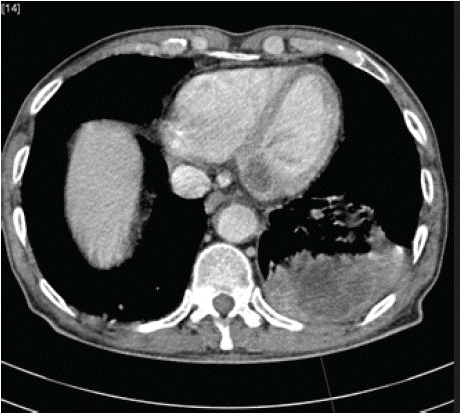

The CT scan showed a left hilar mass syndrome extending 10 cm anteroposteriorly, (Figure A) crossing the midline with multiple lymphadenopathies near the pulmonary artery trunk, as well as a well-defined, oval mass in the left atrium with the same density as the pulmonary mass, in addition to adrenal and brain involvement.

Figure 1: CT scan showed a left hilar mass syndrome extending 10 cm

anteroposteriorly.